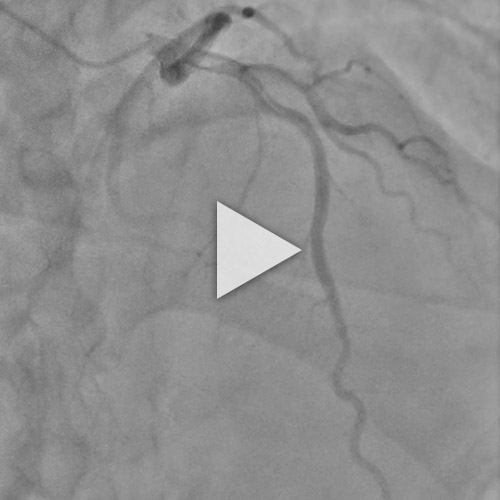

Figure 5 : Suivi du patient - vidéo de coronarographie de contrôle à 3 mois

Le suivi peut s’envisager soit par coronarographie, soit par coroscanner, soit purement clinique.

Nous avons fait le choix de réaliser une coronarographie de contrôle à 3 mois, qui montre une franche régression de cet aspect d’hématome disséquant.